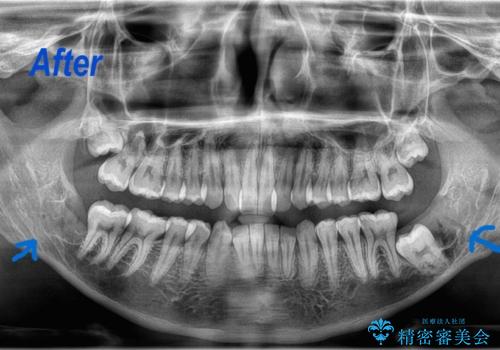

- 当院で矯正治療予定の患者さんです。下顎水平埋伏智歯による下顎第二大臼歯の歯周病やう蝕のリスクを考慮し抜歯をする事になりました。

今回の下顎水平埋伏智歯は歯茎と骨に埋まっていたので、麻酔をした後に歯茎を切開し骨を削って抜歯をしています。抜歯後、糸を縫って1週間後に抜糸に来ていただいています。抜歯後1週間は痛みとお顔の腫れがあり、度合いには個人差があります。